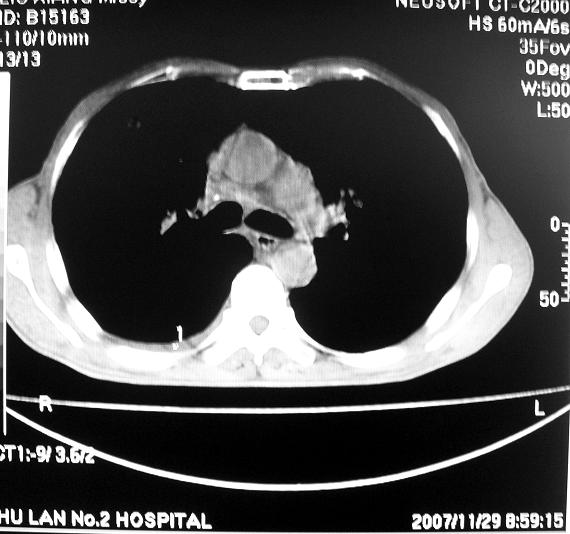

男63岁胸痛来诊

右下肺周围性肺ca并双肺及右侧胸膜转移。[emb6]

右肺病灶前缘不平整,略呈分叶状,其后方胸膜下脂线消失且似有向胸壁浸犯,左下肺球形灶内可见不规则空洞影,余双肺内可见多枚结节影,结合病史支持考虑肺癌肺内转移胸膜转移,便双肺后部病灶倒也是结核好发区域,建议穿刺活检

右下肺周围性肺ca并双肺及右侧胸膜转移。支持

右下肺周围性肺ca并双肺及右侧胸膜转移。

右下肺周围性肺ca并双肺及右侧胸膜转移。单看病变像炎性假瘤。

右下肺癌,双肺及胸膜转移

右下肺癌伴双肺及胸膜转移。

[quote]以下是引用余辉在2007-12-2 20:29:00的发言:[br]右肺病灶前缘不平整,略呈分叶状,其后方胸膜下脂线消失且似有向胸壁浸犯,左下肺球形灶内可见不规则空洞影,余双肺内可见多枚结节影,结合病史支持考虑肺癌肺内转移胸膜转移。

左肺病灶内可见空泡征及典型的胸膜牵拉征,不排除原发周围型肺癌的可能.